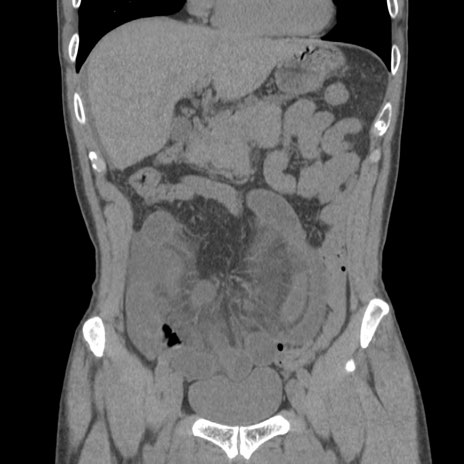

症例56 CT(冠状断像)

横断像